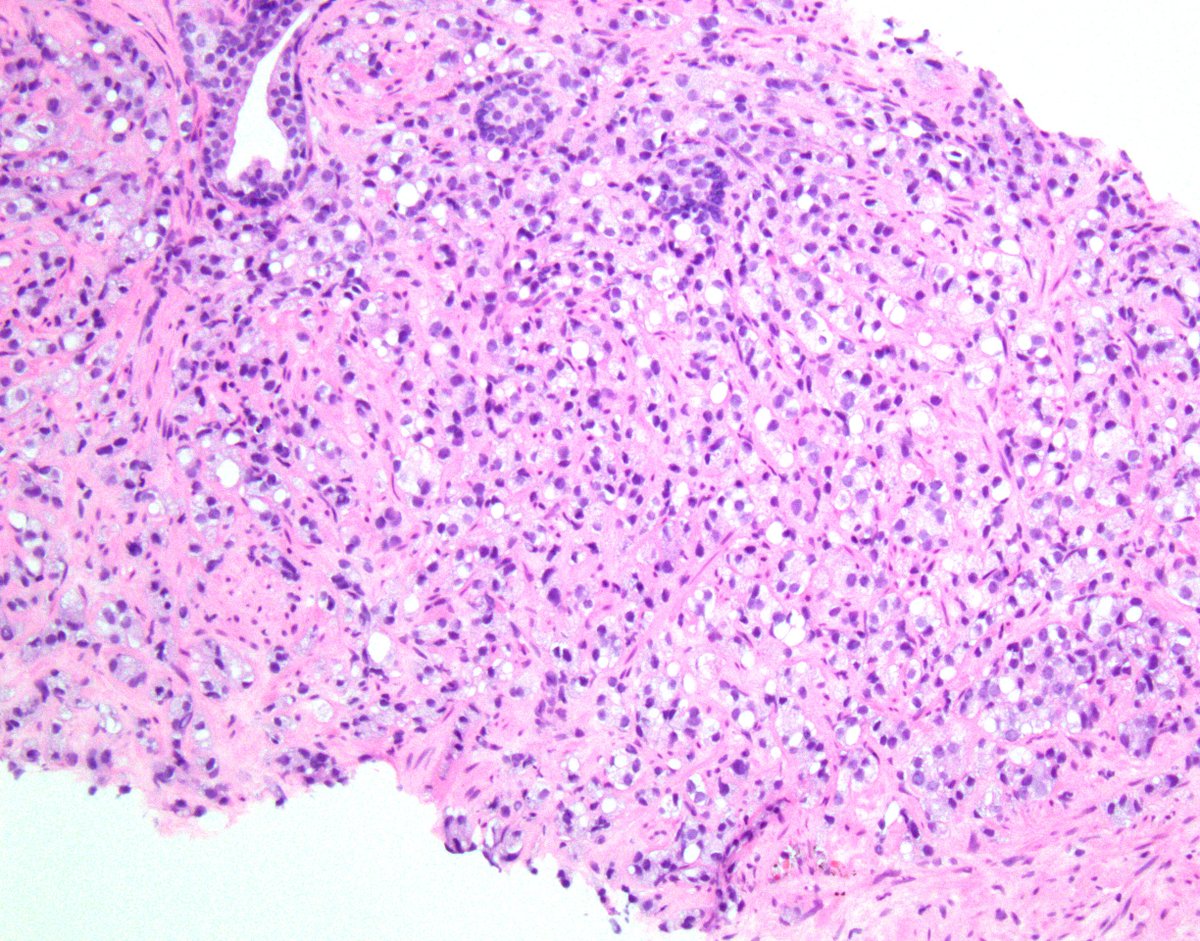

Pathologist at City of Hope specializing in clinical informatics and urological pathology